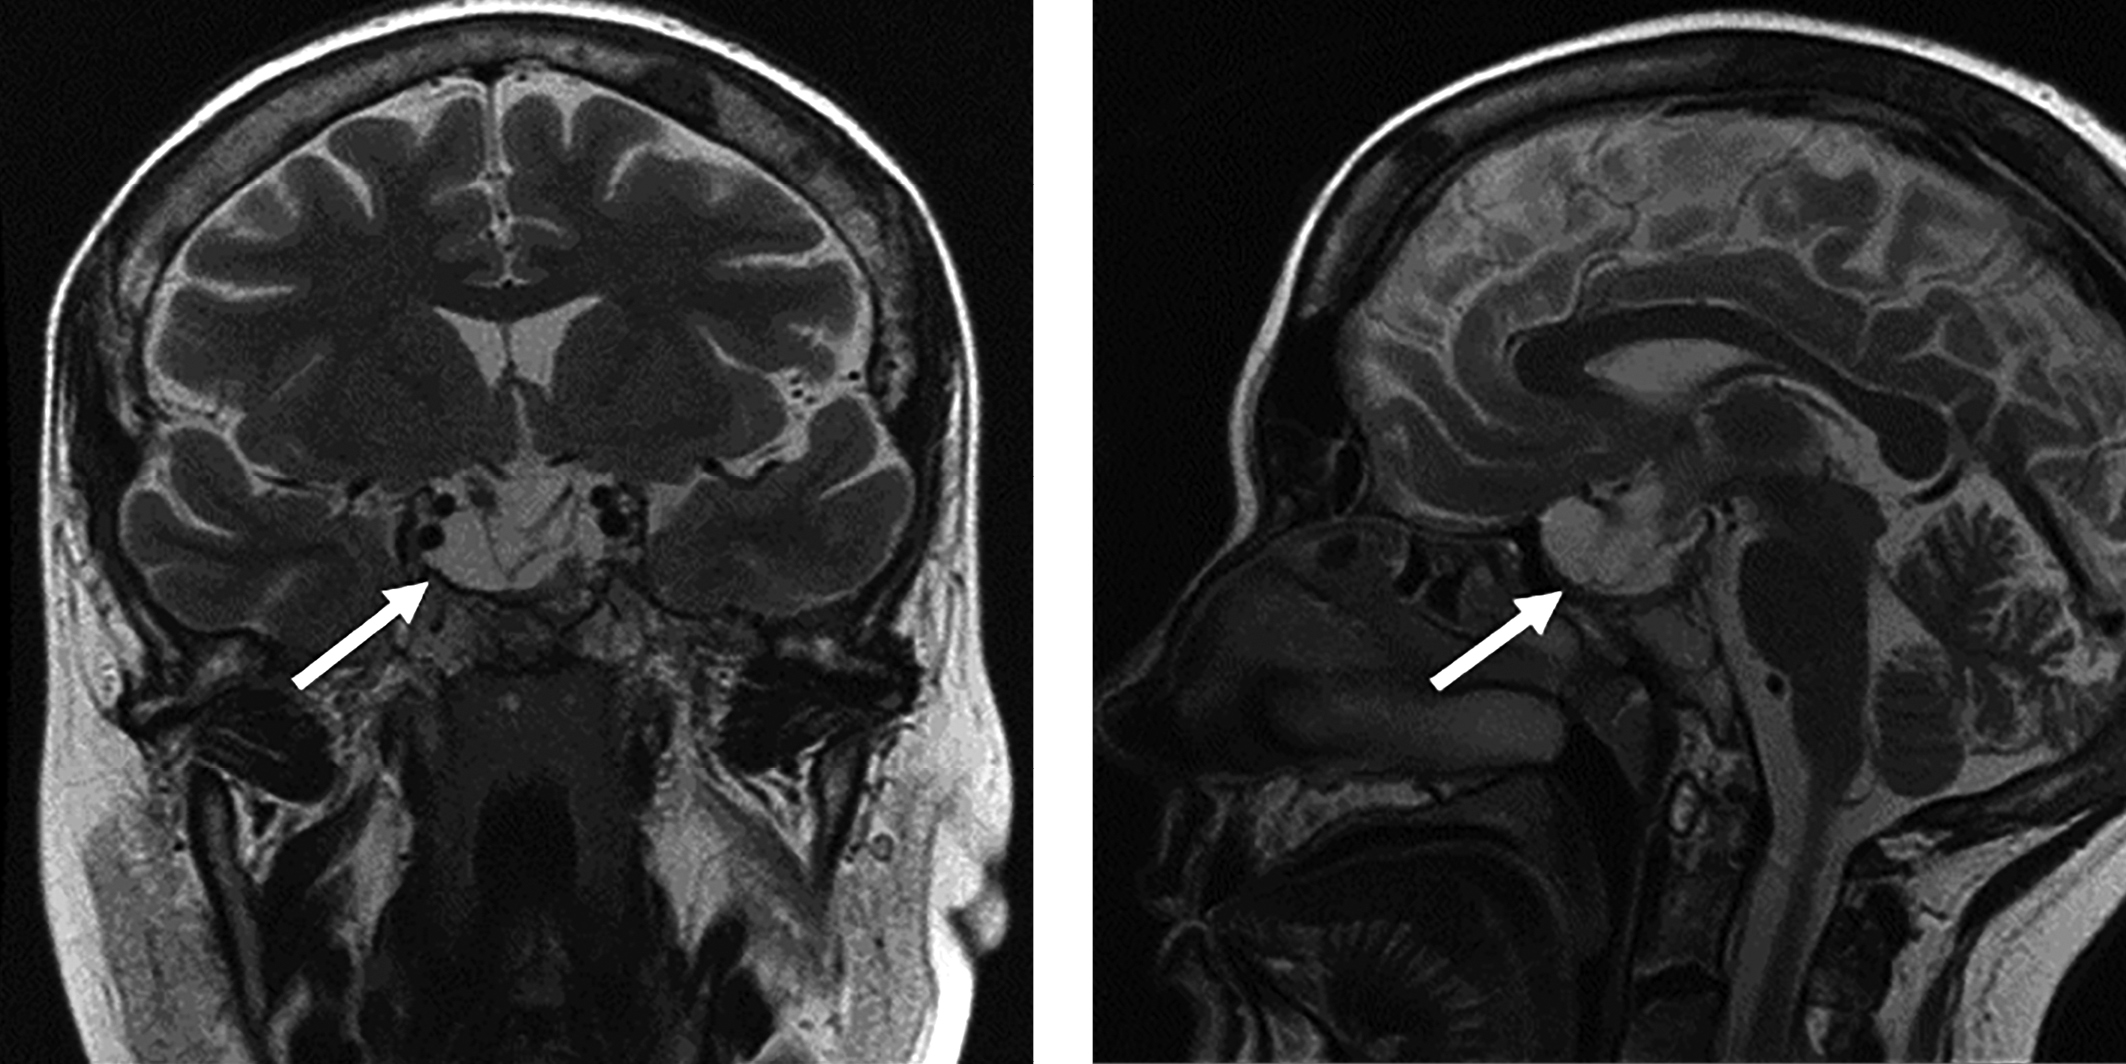

2. Рисунок 2. Магнитно-резонансная томография головного мозга с контрастированием. Стрелкой отмечено образование хиазмально-селлярной области. | |